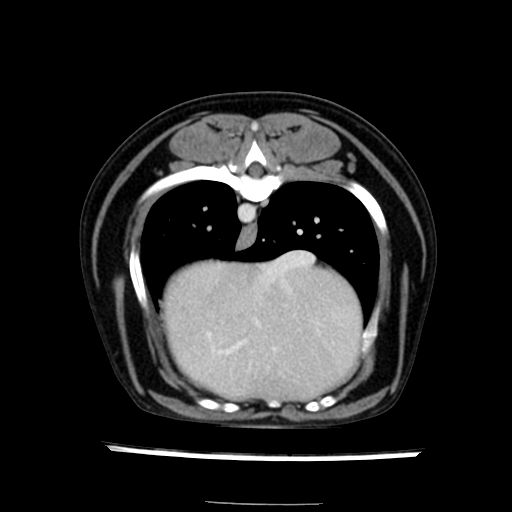

prescritto esame TAC

sequenza immagini limitata al fegato reni e surreni

le immagini ecografiche rispetto alla tac datano circa 7 mesi prima ,le surrenali sono normali nonostante il test acth sia risultato positivo .all’esame TAC dopo diversi mesi risultano aumentate armonicamente nel volume e si individua un forte sospetto di adenoma ipofisario .

sospetto adenoma ipofisario vs. meno probabilmente meningioma della base; intertiziopatia polmonare; lesione espansiva epatica, verosimilmente del lobo laterale sinistro, di sospetta natura neoplastica; lesioni spleniche di natura da definire; iperplasia/ipertrofia delle ghiandole surrenali, bilateralmente; vertebra di transizione del rachide toracico; tenosinovite cronica del muscolo bicipite brachiale di destra.

la tac dopo 7 mesi permette misure tridimensionali 5,2 x 9,2 x 4,5 cm (forma piu’ allungata )